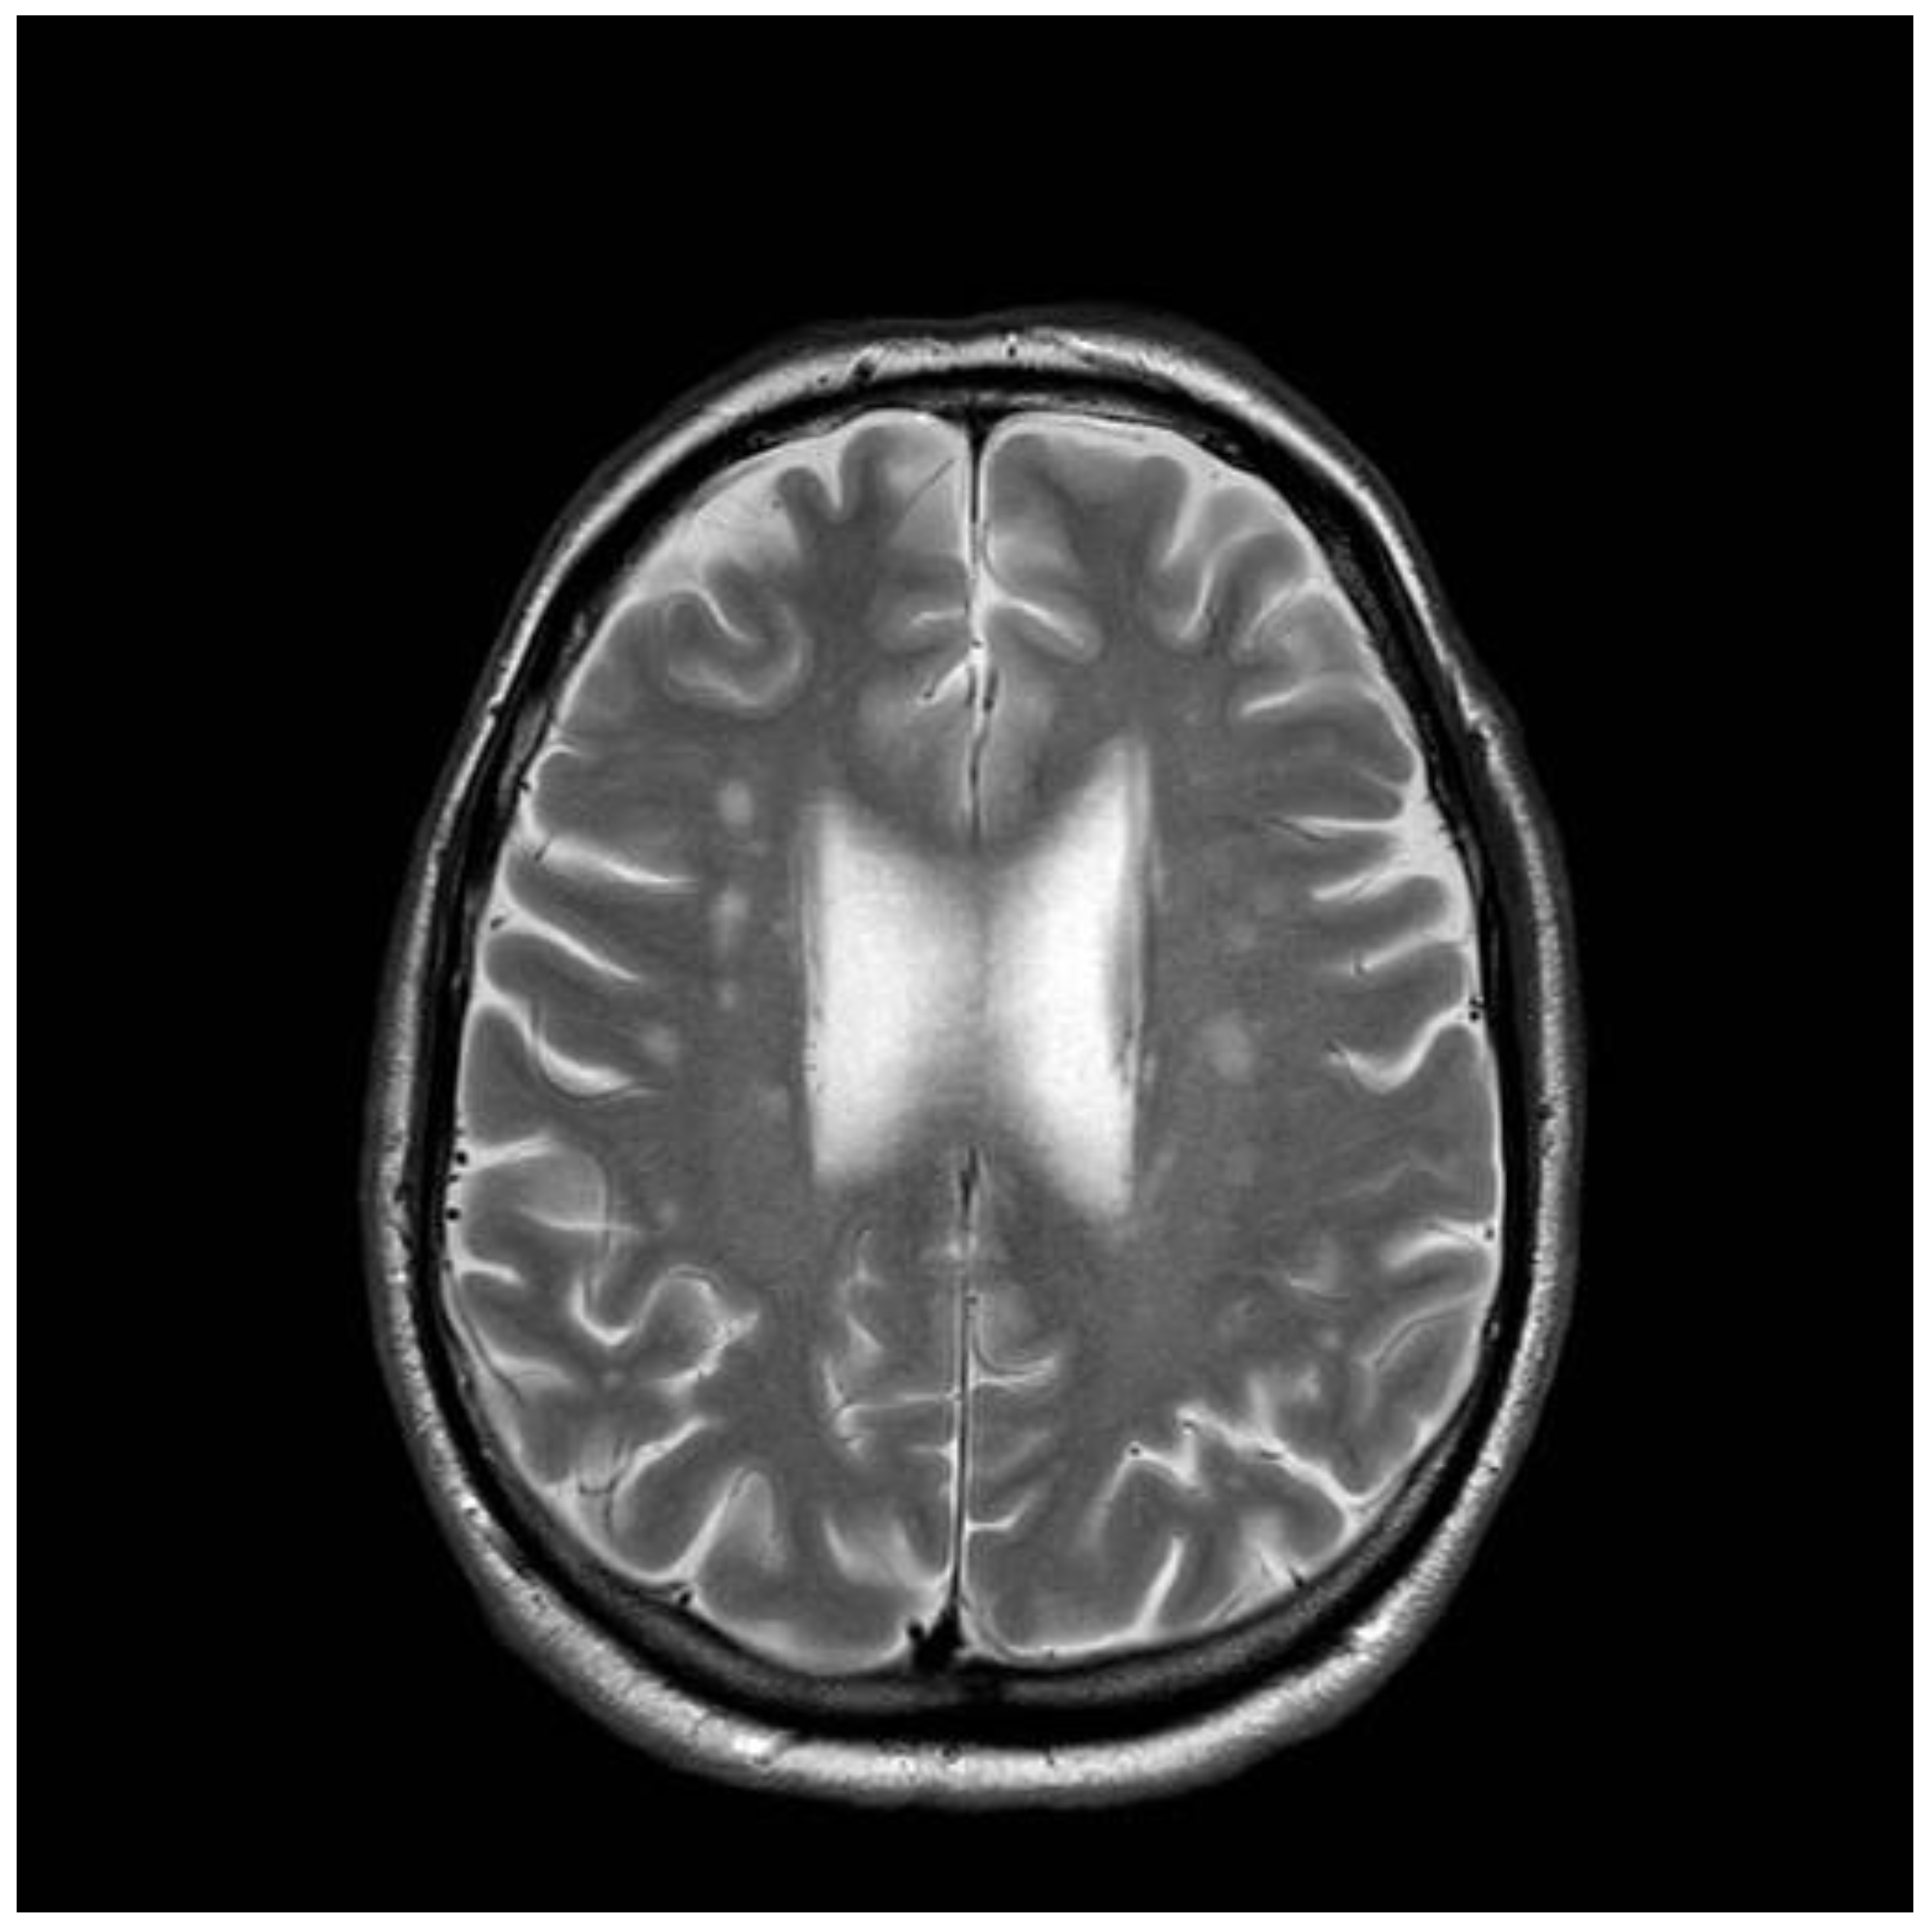

Figure 4. Brain MRI scan conducted on the same patient, as in Figure 3. The scan was conducted in 2018 and at that point showed evidence of cerebellar atrophy that apparently developed over an interval of 21 years. The patient now displays clinical evidence of cerebellar ataxia.

4. Predictive Value of Different Transglutaminase Antibodies: An Illustrative Case

A 41-years old man presented to neurology in 1997, with intractable headaches for the previous 2 years. He described them as severe, often unilateral and throbbing, lasting for several days and often associated with focal but transient neurological deficits (e.g., hemisensory disturbance and double vision). He also complained of memory difficulties and inability to concentrate. Brain MRI was done to rule out any ischemic cerebrovascular events. This showed white matter changes not typical of stroke or inflammation but of undetermined clinical significance (Figure 3). He had no vascular risk factors. He was started on aspirin and discharged. Subsequent outpatient clinical review showed ongoing symptoms of headache, and poor concentration and compromised memory function interfering with his everyday activities. Additional investigations at that stage ruled out systemic lupus erythematosus (SLE) and antiphospholipid syndrome. Cardiac echo and 24-h cardiac recordings, as well as vascular imaging were normal. Blood tests (available at that time) found him to be positive for anti-gliadin (AGA) and EMA antibodies. Duodenal biopsy confirmed the presence of gluten-sensitive enteropathy. It was thought that the headaches and MRI changes were secondary to CD (gluten encephalopathy) [12]. The patient was given advice for GFD by an experienced dietitian. He was followed up at regular intervals (every six months). Initial review after being on the diet for 6 months showed significant improvement in his headaches and cognitive difficulties. His adherence to the GFD over subsequent years was intermittent for a number of reasons—he could not afford gluten-free products, family problems and housing issues, and a one-year spell in prison. During this period, his antibody profile remained positive. He continued to be reviewed by the dietitian and attempts were made to ensure strict adherence to GFD. In 2006, he completely abandoned the GFD, but he restarted it a year later. He gave up the diet again in 2009. A few months later, he presented with an itchy vesicular rash over his arms and face. Dermatological review and skin biopsy confirmed the diagnosis of DH. He was still consuming gluten and serological testing for TG2 IgA, EMA, and anti-gliadin antibodies confirmed the presence of CD-related antibodies. He remained symptomatic with frequent headaches. More recently, he developed a degree of gait incoordination and a tendency to fall. He also complained of distal sensory disturbance with a burning feeling in his feet, less so in his hands. Further brain imaging showed evidence of cerebellar atrophy (Figure 4) that was not present in the baseline scan. Neurophysiological assessment including thermal threshold studies confirmed the presence of small fiber neuropathy.

Serum from this patient was stored at the time of the diagnosis of gluten encephalopathy (1998), and was subsequently available for testing for TG2, TG3, and TG6 autoantibodies, when these serological tests became available [7,13]. The tests showed him to be positive for deamidated gliadin peptide antibodies (IgA/IgG) and, interestingly, all 3 types of transglutaminase autoantibodies (TG2 IgA/IgG, TG6 IgA, and TG3 IgA/IgG). The TG2 antibody positivity would be expected on the basis of CD. TG6 antibody positivity would be in keeping with the diagnosis of gluten encephalopathy and the subsequent development of cerebellar ataxia (gluten ataxia) and neuropathy (gluten neuropathy), due to poor adherence to a GFD. The positive anti-TG3 antibody result from the 1998 sample would explain the subsequent development of DH, which however, manifested in 2009, over 10 years after the initial presentation with the neurological complaints. The patient is still under regular review and during his last attendance (August 2020) he tested positive for TG2, EMA, AGA, and TG6 IgG and IgA antibodies. AGA and TG2 antibodies were tested throughout his clinic appointments and were always positive. An observed reduction of the TG2 titer was only seen in 2008 and 2016, whilst he was trying to be strict with his GFD.